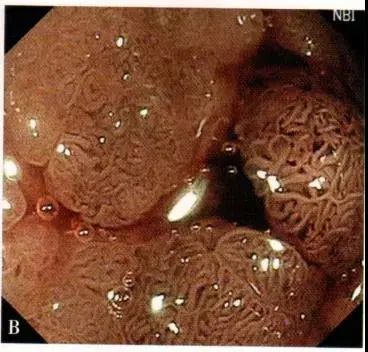

大咖总结内镜下识别早期大肠癌这些很关键

结肠腺瘤内镜图

这样的肠镜表现如何诊断